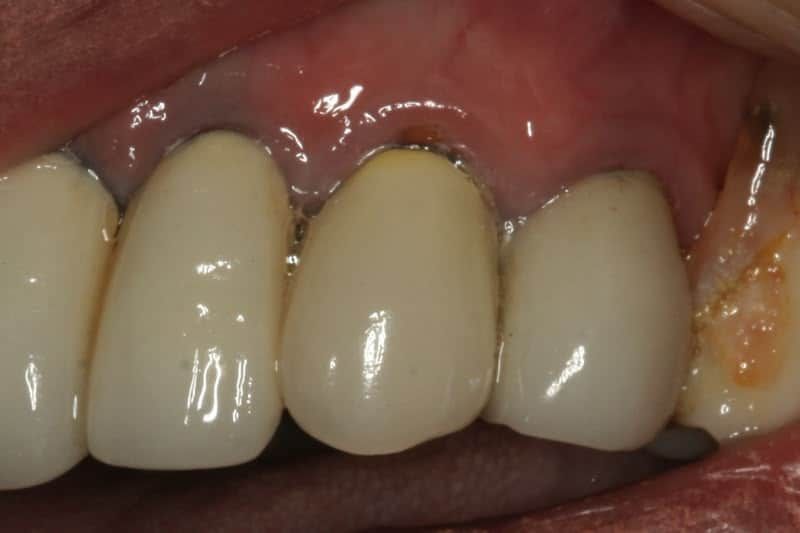

This case is more recent & was completed in March 2019. This gentleman’s Maryland bridge, as it’s called, was more than 30 years old , and still in (mostly) great shape. Unfortunately, he fell and hit a front tooth, breaking off a big piece. For perspective, that bridge was done 9 years before I became a dentist. It was done the year before I started college! The oldest and still functioning dental work I’ve done that I know of, is a 19 year old CEREC crown for my Mom. 🙂 Anyway, back to the story…..

Given the bridge is still solidly cemented and functioning, I sure didn’t want to replace it. The patient didn’t want to spend that much money either. So I suggested an overcrown for him, too. This time, we did it with with our CEREC Bluecam CAD/CAM system. True, it is “old “technology, but it’s still among the best available. We chose a material called Celtra DUO for its strength, esthetics, and because it matched color so well.

The process was similar to the previous case, but instead of taking a mold and sending it to the lab, we sprayed a thin coat of blue powder over the teeth, scanned it, designed it on the Bluecam, milled it, polished it, and bonded it in. The whole process lasted about 75 minutes. No numbing, only a little drilling, and a little polishing afterwards. Not too shabby, if I do say so myself. 😀